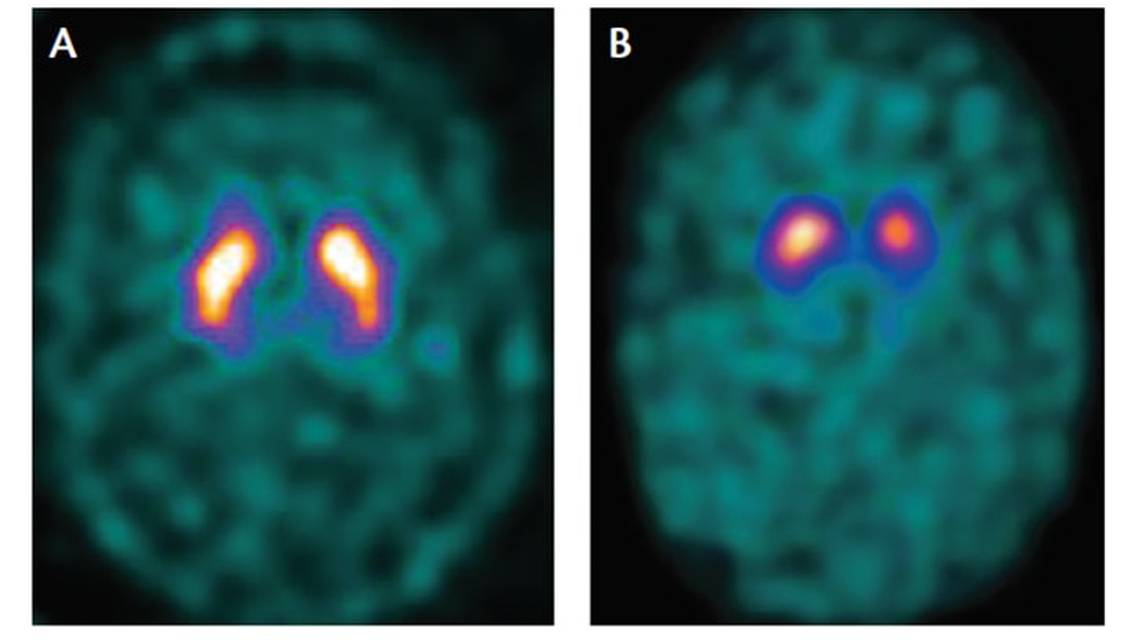

The core clinical signs of PD include resting tremor, bradykinesia, rigidity, and postural instability. Most patients also experience nonmotor symptoms such as cognitive and emotional changes (apathy, depression, cognitive deficits), dysautonomia, sleep disorders, and sensory disturbances. Many experience prodromal nonmotor symptoms such as anosmia, depression, constipation, and REM sleep behavior. Clinical subtypes of the disease have been identified, including tremor dominant and postural instability gait difficulty (PIGD). Atypical features (eg, rapidly progressive disease course, upper motor neuron signs, and poor or unsustained response to levodopa therapy) may be clues that there are other etiologies that can be differentiated with imaging studies.1 Structural brain imaging (eg, CT or MRI) is frequently ordered to investigate these cases. In addition, SPECT imaging with DaT may be useful to confirm central nervous system (CNS) dopamine signaling deficiency in select cases (Figure 1). On DaT scans, normal radiotracer uptake in the striatum (caudate nucleus and putamen) forms 2 crescent-shaped regions of activity, mirrored around the median plane. In contrast, in PD, there is asymmetrically decreased activity in the putamen, often with preserved uptake in the caudate nucleus.2,3 A DaT scan is FDA approved for differentiating essential tremor from PD, and is also frequently useful for differentiating drug-induced parkinsonism from PD.